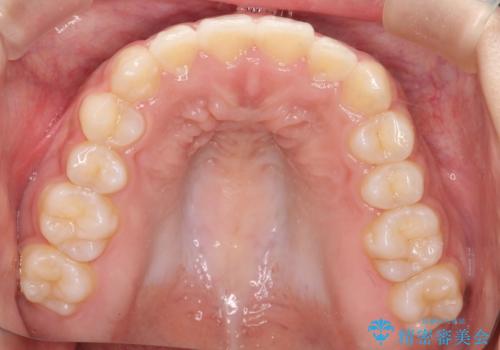

インビザライン 前歯のがたつきを目立たず矯正

- 前歯のがたつきが気になるとのことで来院されました。

インビザラインにて治療を行いました。

わずかに歯と歯の間に隙間を作り、歯列矯正を行いました。

マウスピースをしっかりと使用していただけたので、スムーズに治療を終了することができました。